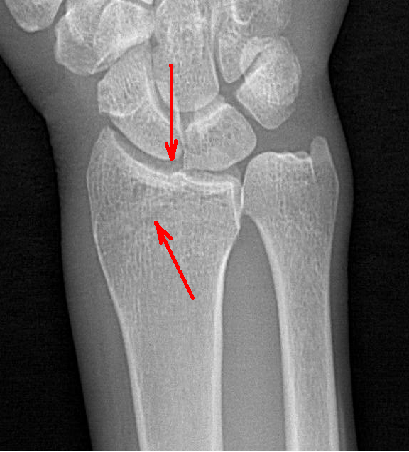

在常規(guī)拍片中,往往由于影像的重疊或體位等因素造成病灶部位漏診,而動(dòng)態(tài)DR具有可視化功能,可以進(jìn)行動(dòng)態(tài)觀察,毫秒級(jí)高清點(diǎn)片,更快捕捉到病灶點(diǎn),大大降低漏診誤診幾率。比如,在常規(guī)拍片中易漏診的心臟后病灶、膈肌病變、隱匿肋骨骨折和小兒支氣管異物檢查等,在動(dòng)態(tài)DR攝影中都有很高的確診率。

隱匿性骨折高清圖像